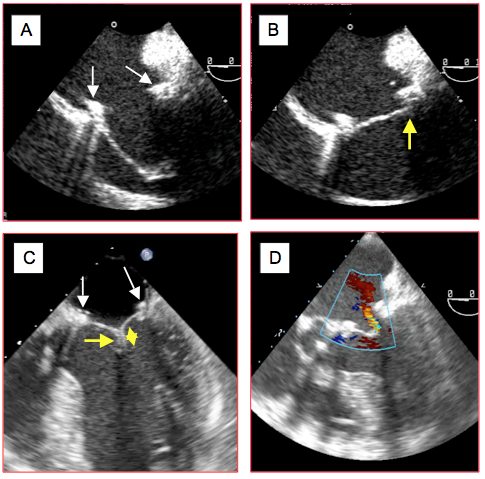

Figure 26.49 : Images ETO après plastie mitrale. A : après résection large de P2 et plastie du feuillet postérieur, toute l’occlusion est assurée par le feuillet antérieur ; sa longueur doit dépasser le diamètre de l’anneau (flèches blanches) et permettre un affrontement sous le feuillet postérieur pour que la valve soit occlusive. B : occlusion satisfaisante du feuillet antérieur en butée sous le feuillet postérieur et l’anneau en systole. C : la coaptation des feuillets doit se faire sur une hauteur d’au moins 5 mm (flèche jaune) pour assurer l’étanchéité, ce qui est le cas ici après une plastie et résection du feuillet antérieur. D : fuite résiduelle après plastie mitrale ; si elle est pansystolique, cette fuite est excessive car le jet présente une largeur significative au passage de la valve.